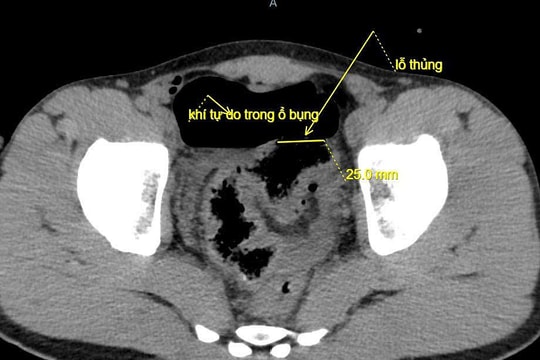

Dùng vòi nước rửa ôtô xịt hậu môn gây thủng đại tràng

Người đàn ông 30 tuổi dùng vòi nước rửa ôtô (áp lực cao) xịt vào hậu môn làm thủng đại tràng, nhập viện cấp cứu.